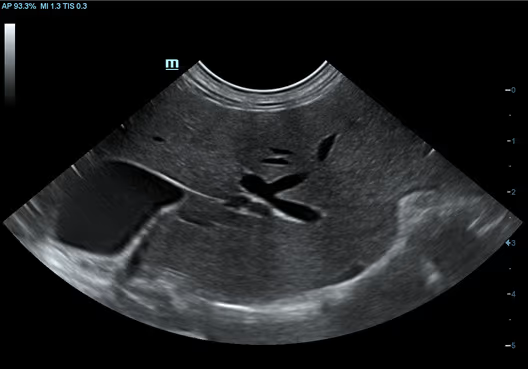

Köpek Böbreği

Köpek Böbreği

Kedi Karaciğeri

Kedi Karaciğeri

Hepatik Akış

Hepatik Akış